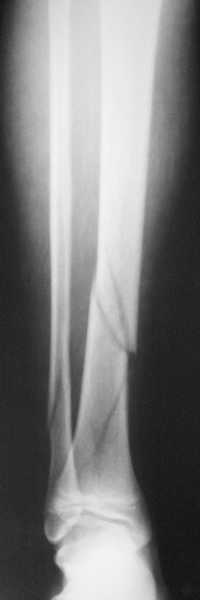

Уважаемый коллега! Обычно, хирургичское лечение переломов пилона начинают с остеосинтеза малоберцовой кости (чего не продемонстрировали коллеги из Новокузнецка). В Вашем случае нет убедительных данных за перелом малоберцовой кости, так что, видимо, этот этап вы пропускаете. После чего переходят собственно к пилону - основные усилия в лечении которого необходимо направить на устранение импрессии (отчетливо видна на боковой R-грамме), затем пластика дефекта ну и накостный остеоинтез платиной, коих достаточно много. Хотел бы предостеречь Вас от: закрытой "малоинвазивной" техники в данном случае, так как для устранения импрессии малоинвазивно необходим определенный опыт и начинать с этого я бы не стал, использовать пластину Pilon Plate-имплант сложный в установке и , опять же, требует определенных навыков. Я бы синтезировал традиционной пластиной "лист клевера" с угловой стабильностью.

Есть смысл начать с наложения дистрактора голень-стопа. Лигаментотаксис может очень существенно помочь с репозицией. При переломе малоберцовой кости этот подход позволяет не тратить время на ее остеосинтез. Больших участков импрессии суставной поверхности не видно, перелом больше по типу раскалывания. Это делает возможной полностью закрытую репозицию с фиксацией либо аппаратом, либо компрессирующими винтами и аппаратом, либо пластиной малоинвазивно.

Напомню, речь идет не о переломе лодыжек, тут механизм травмы другой, и малоберцовая может вообще быть целой при тяжелых разрушениях дистального конца большеберцовой.

В данном случае ориентир сохранен, малоберцовая хорошо сочленена с тараном. Но несмотря на отсутствия перелома на снимке, все-таки для страховки можно было бы сделать снимок проксимальной части конечности.